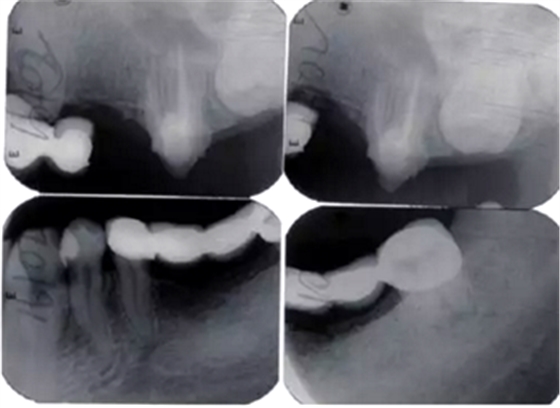

4.修復(fù)治療:

術(shù)后2周進行重新牙體預(yù)備,制作并戴入臨時修復(fù)體,牙齦塑形(圖6)。術(shù)后3個月,上前牙牙齦形、線、點位置基本穩(wěn)定,進行永久修復(fù)。上頜采用烤瓷固定橋修復(fù),樁核冠單冠修復(fù),下頜固定-活動義齒修復(fù),恢復(fù)良好的牙齒外形和接觸區(qū)、重建完整牙列、恢復(fù)口腔功能、改善美學(xué)效果(圖7)。